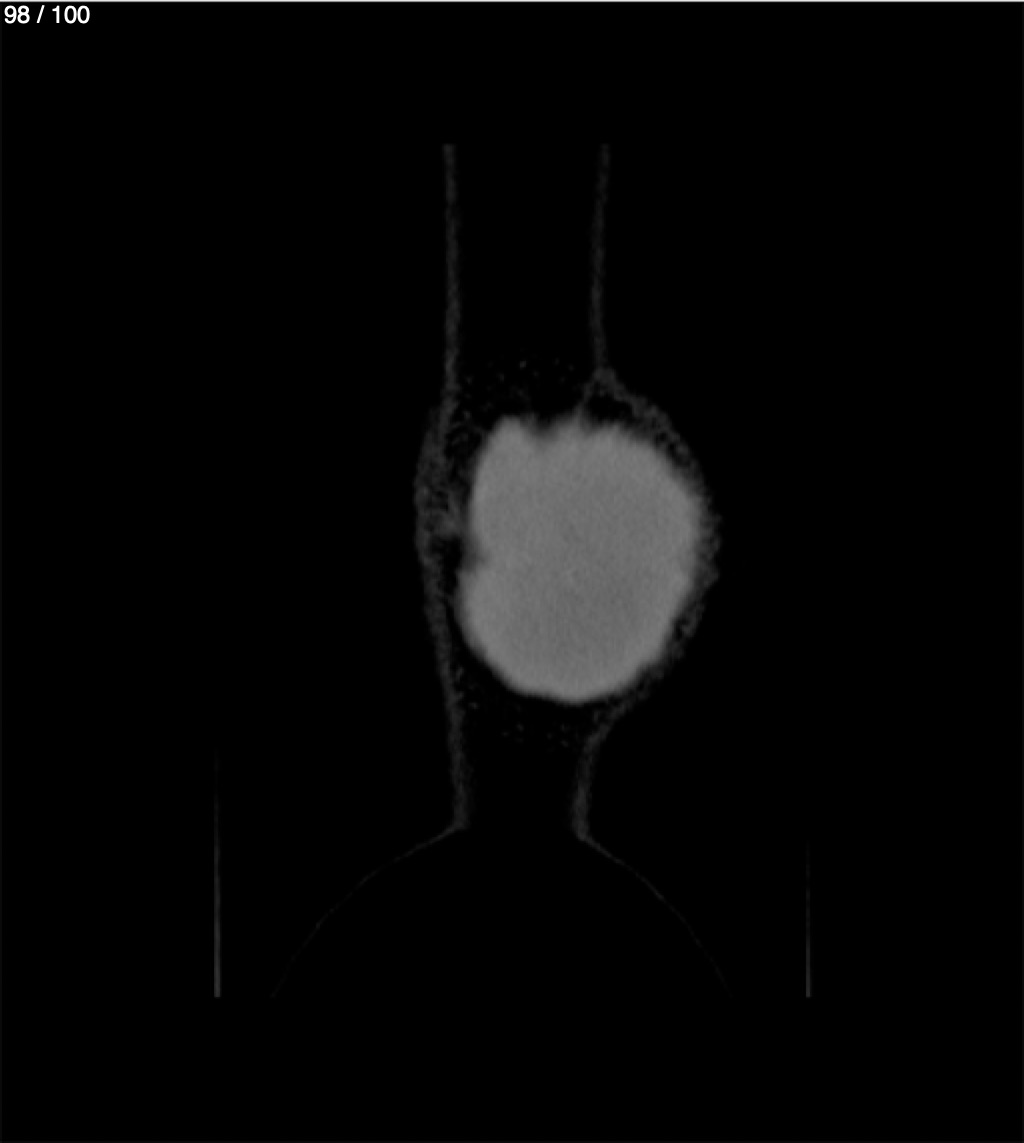

Yonelly Barrios Diaz 35A - T.C Craneo